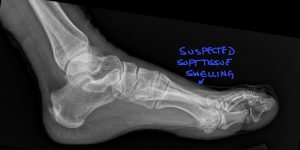

Fig. 4 Annotated lateral foot x-ray showing soft tissue swelling over the dorsal forefoot.

• Callus Formation: Hazy, cloud-like radio-opacity surrounding the fracture site (seen in this case study).

Conclusion: DACBR Radiology Reports and Second Opinions can Improve Patient Care